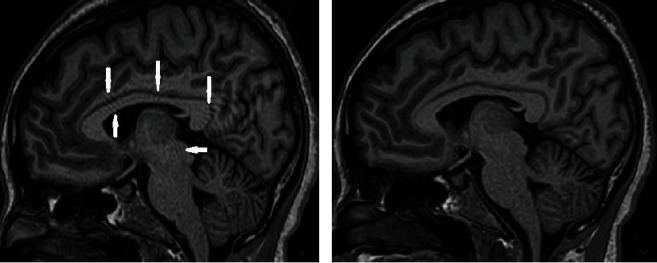

Background: The 3D T1W turbo field echo sequence is a standard imaging method for acquiring high-contrast images of the brain. However, the contrast-to-noise ratio (CNR) can be affected by the turbo factor, which could affect the delineation and segmentation of various structures in the brain and may consequently lead to misdiagnosis. This study is aimed at evaluating the effect of the turbo factor on image quality and volumetric measurement reproducibility in brain magnetic resonance imaging (MRI).

Methods: Brain images of five healthy volunteers with no history of neurological diseases were acquired on a 1.5 T MRI scanner with varying turbo factors of 50, 100, 150, 200, and 225. The images were processed and analyzed with FreeSurfer. The influence of the TFE factor on image quality and reproducibility of brain volume measurements was investigated. Image quality metrics assessed included the signal-to-noise ratio (SNR) of white matter (WM), CNR between gray matter/white matter (GM/WM) and gray matter/cerebrospinal fluid (GM/CSF), and Euler number (EN). Moreover, structural brain volume measurements of WM, GM, and CSF were conducted.

Results: Turbo factor 200 produced the best SNR (median = 17.01) and GM/WM CNR (median = 2.29), but turbo factor 100 offered the most reproducible SNR (IQR = 2.72) and GM/WM CNR (IQR = 0.14). Turbo factor 50 had the worst and the least reproducible SNR, whereas turbo factor 225 had the worst and the least reproducible GM/WM CNR. Turbo factor 200 again had the best GM/CSF CNR but offered the least reproducible GM/CSF CNR. Turbo factor 225 had the best performance on EN (-21), while turbo factor 200 was next to the most reproducible turbo factor on EN (11). The results showed that turbo factor 200 had the least data acquisition time, in addition to superior performance on SNR, GM/WM CNR, GM/CSF CNR, and good reproducibility characteristics on EN. Both image quality metrics and volumetric measurements did not vary significantly (p > 0.05) with the range of turbo factors used in the study by one-way ANOVA analysis.

Conclusion: Since no significant differences were observed in the performance of the turbo factors in terms of image quality and volume of brain structure, turbo factor 200 with a 74% acquisition time reduction was found to be optimal for brain MR imaging at 1.5 T.